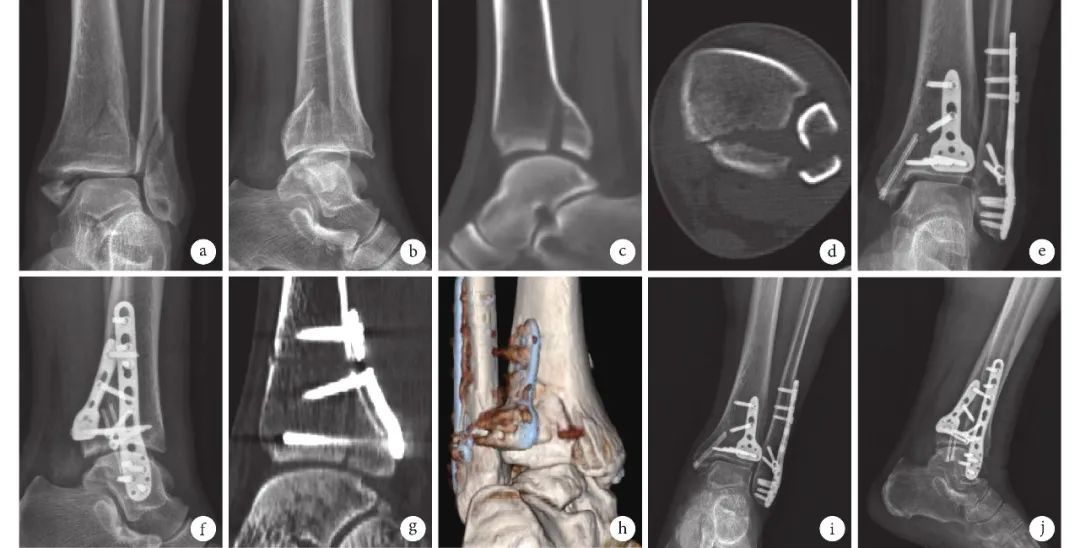

【汤汤播报】车祸导致内外后三踝骨折,罗雪平团队接骨断续

外踝 后踝骨折

踝部骨折后踝骨折块的4种类型

踝关节骨折